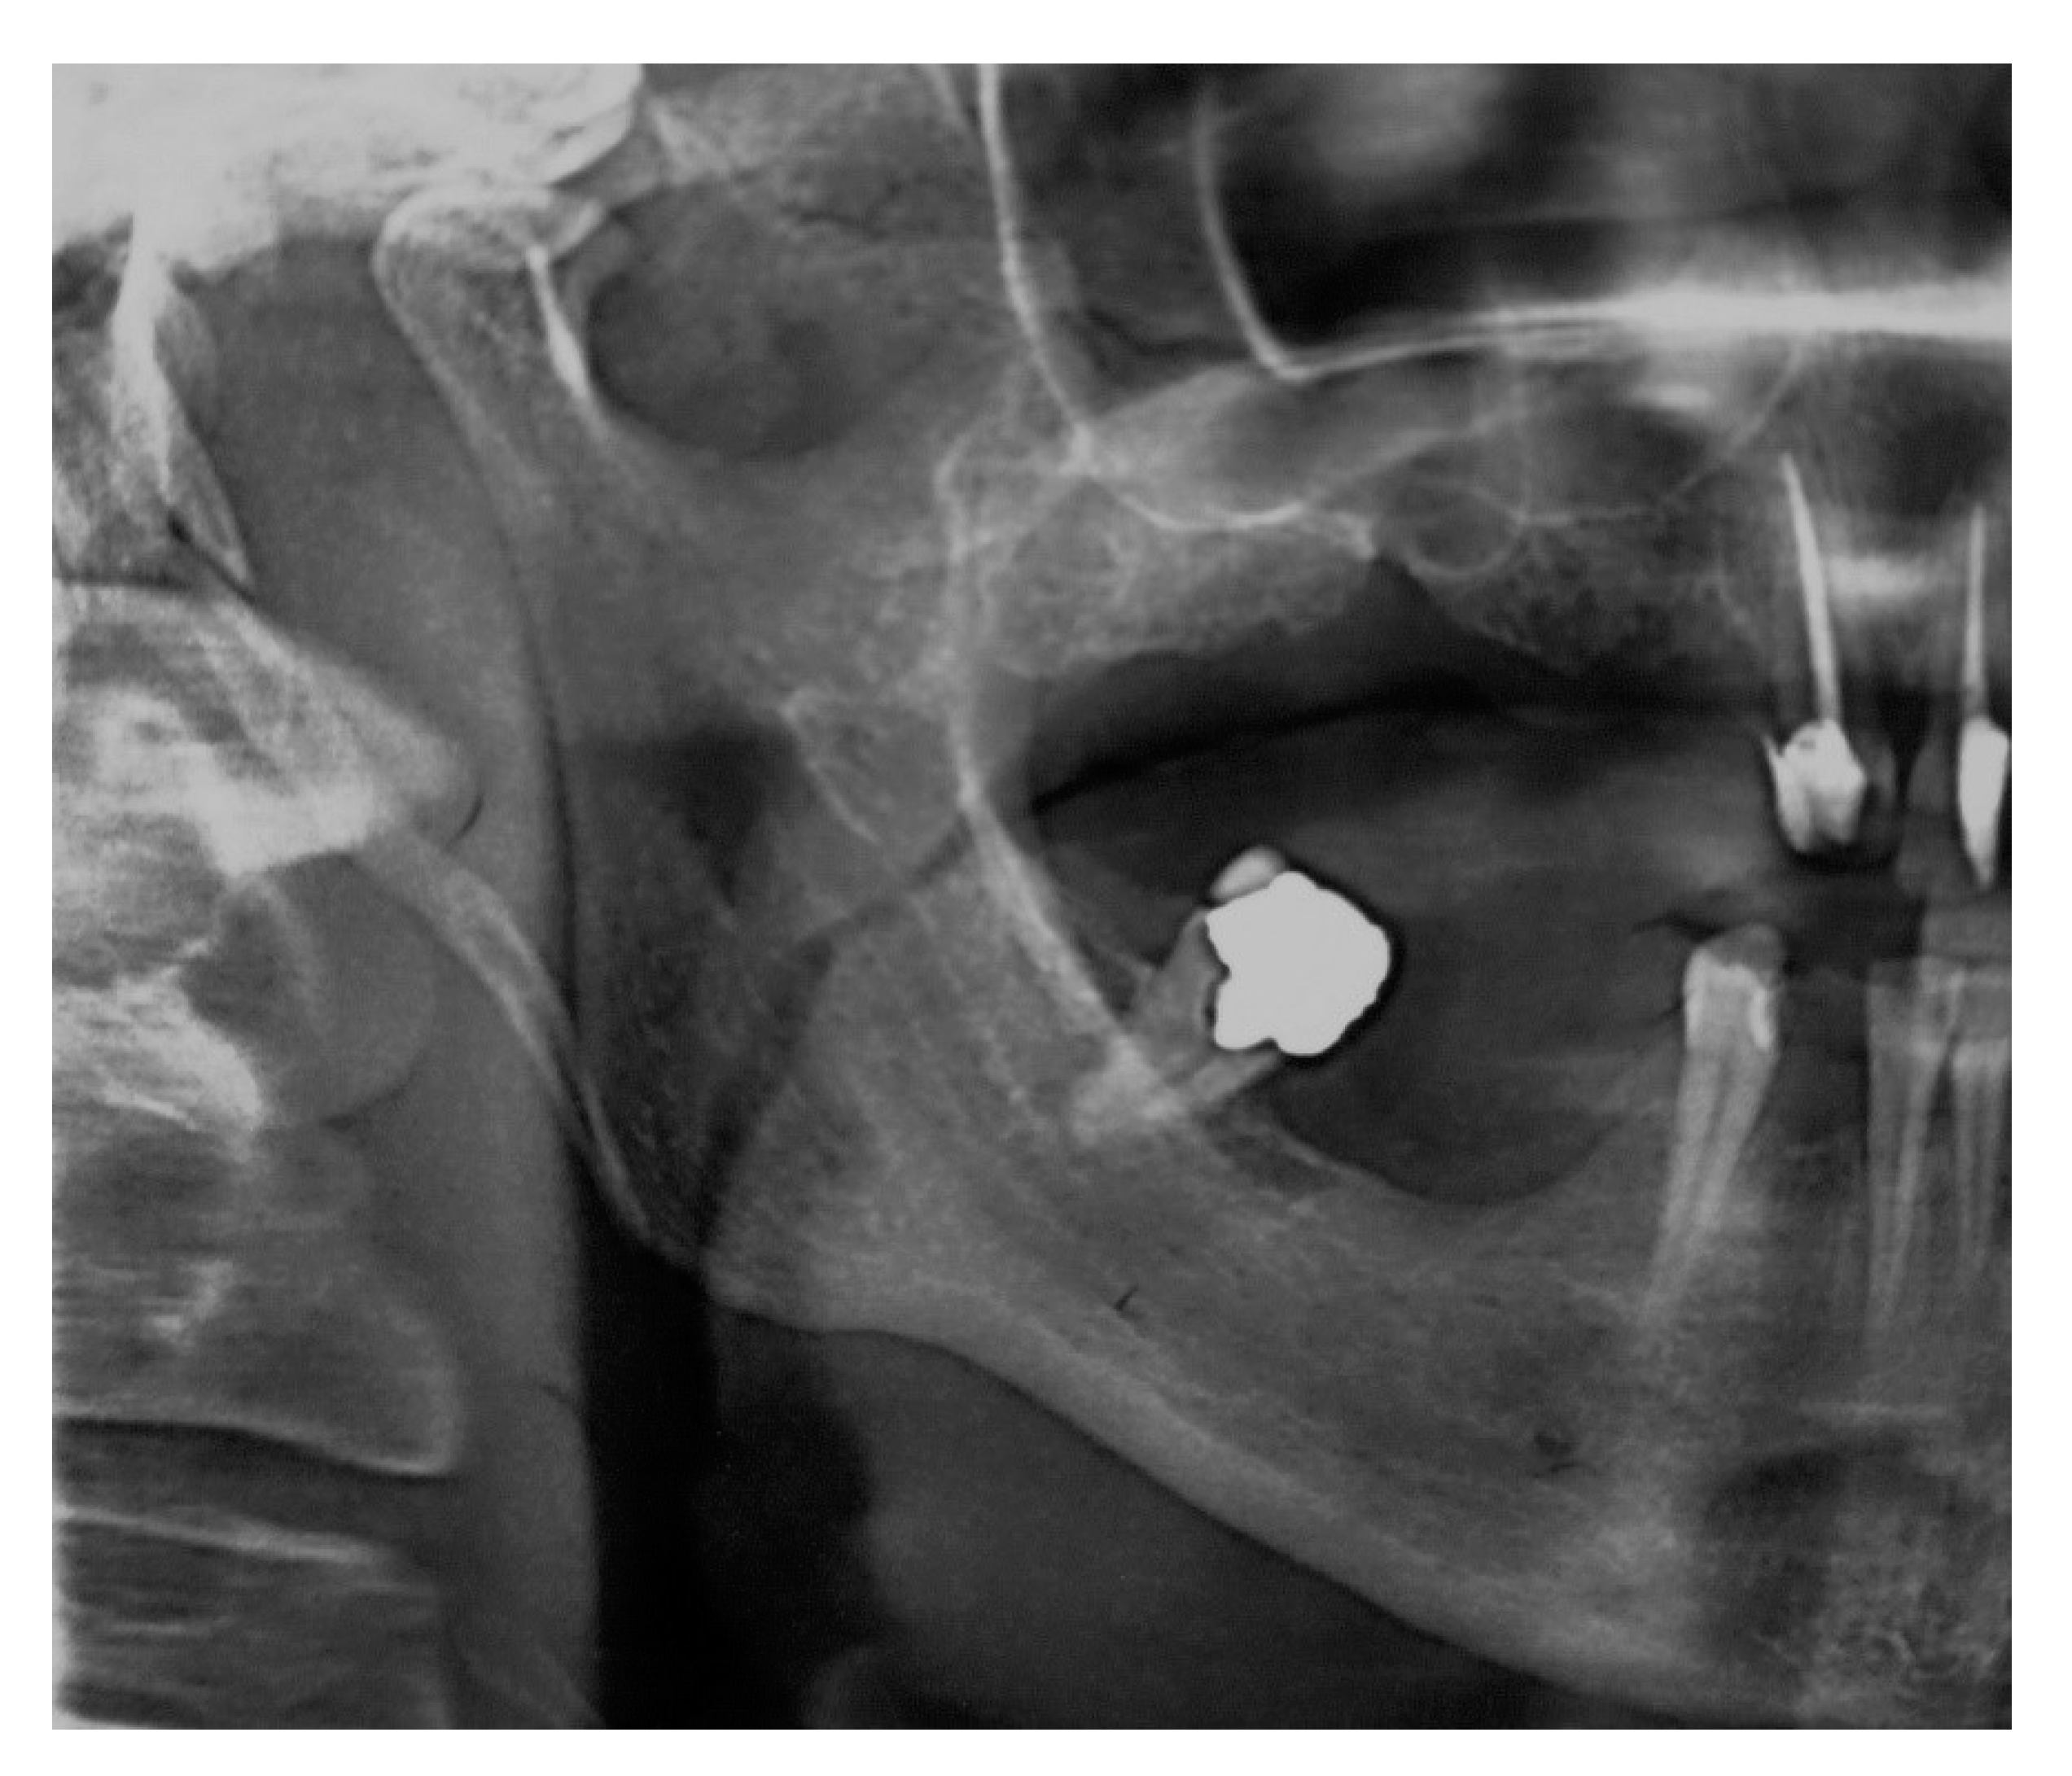

Apart from these findings, there were multiple astonishing CBCT images of the different planes, which show an impressive bilateral mineralization of the styloid complex. All the taken CBCT radiographic images showed a “collar-like” multi-interrupted and segmented calcified stylohyoid complex (SHC). On the left side, the segmented calcified styloid ligaments fully stretched to the lesser cornu of the hyoid bone and on sagittal CBCT images, measuring 85.87 mm in length with an average width of 3.63 mm, while the right side barely reached the lesser horns of the hyoid bone, measuring 81.13 mm in length with an average width of 2.58 mm (Figure 5).

Due to suspicion that this patient belongs to the Eagle’s syndrome group, additional angle measurements were performed. The measurements of important angles for 3D visualization of the SHC showed: right 53.54° (short) and left 66.8° (~normal) for the mediolateral angle (MLA), right 80.63° and left 78.78° (elongated) for the anteroposterior angle (APA), indicating wide both angles [9]. Measurements of maximum thickness with values of 4.56 mm and 3.6 mm (normal) for the right and left sides were seen, respectively. On both sides, the pattern of calcification/mineralization was almost identical, involving the tympanohyal, stylohyal, ceratohyal and hypohyal parts of the SHC (Figure 6).

The diagnosis of “mimicking Eagle’s” syndrome is made due to the results of the 3–D left mediolateral angle (MLA) measurement, which showed a normal range on the left side with the value of 66.80° (~normal), with wide anteroposterior angle (APA), so we concluded by using 3–D CBCT visualization and MLA and APA measuring, that this case is “mimicking” but not a true Eagle’s case. The unilateral pain then must have come from another origin, which was an impacted maxillary canine in our case. The term “mimicking” is a literary term, which describes, in this case, a mimicking of a true painful Eagle’s syndrome with the pain origin due to pressure of the mineralized stylohyoid complex (SHC) on the neck’s nerves. Contributing to our proper diagnosis of mimicking Eagle’s syndrome is a pain free clinical course after surgical extraction of the maxillary impacted canine; all patient’s pain complaints disappeared within a few postoperative weeks, which means that there was no pressure on the vital neurological and vascular anatomic neck elements and it is more likely that the pain episodes were provoked and caused by the impacted maxillary canine.

The CBCT acquisition performed on patient #2 showed remarkable images of a segmented and completely calcified bilateral SHC, proving the necessity for CBCT imaging as an essential tool in the diagnosis of the cause of pharyngodynia, suspecting Eagle’s syndrome [17]. According to Langlais et al. [16], the pathological mineralization of the styloid complex is radiographically classified into three types. Type I is the elongated uninterrupted styloid process (more than 30 mm); type II is the pseudo-articulated styloid complex with stylo-mandibular and stylohyoid ligaments joined to the styloid process; and type III is the segmented and mineralized styloid complex. This classification could lead us to a diagnosis of the left type II and right type III mineralized styloid ligaments, in this case [15].